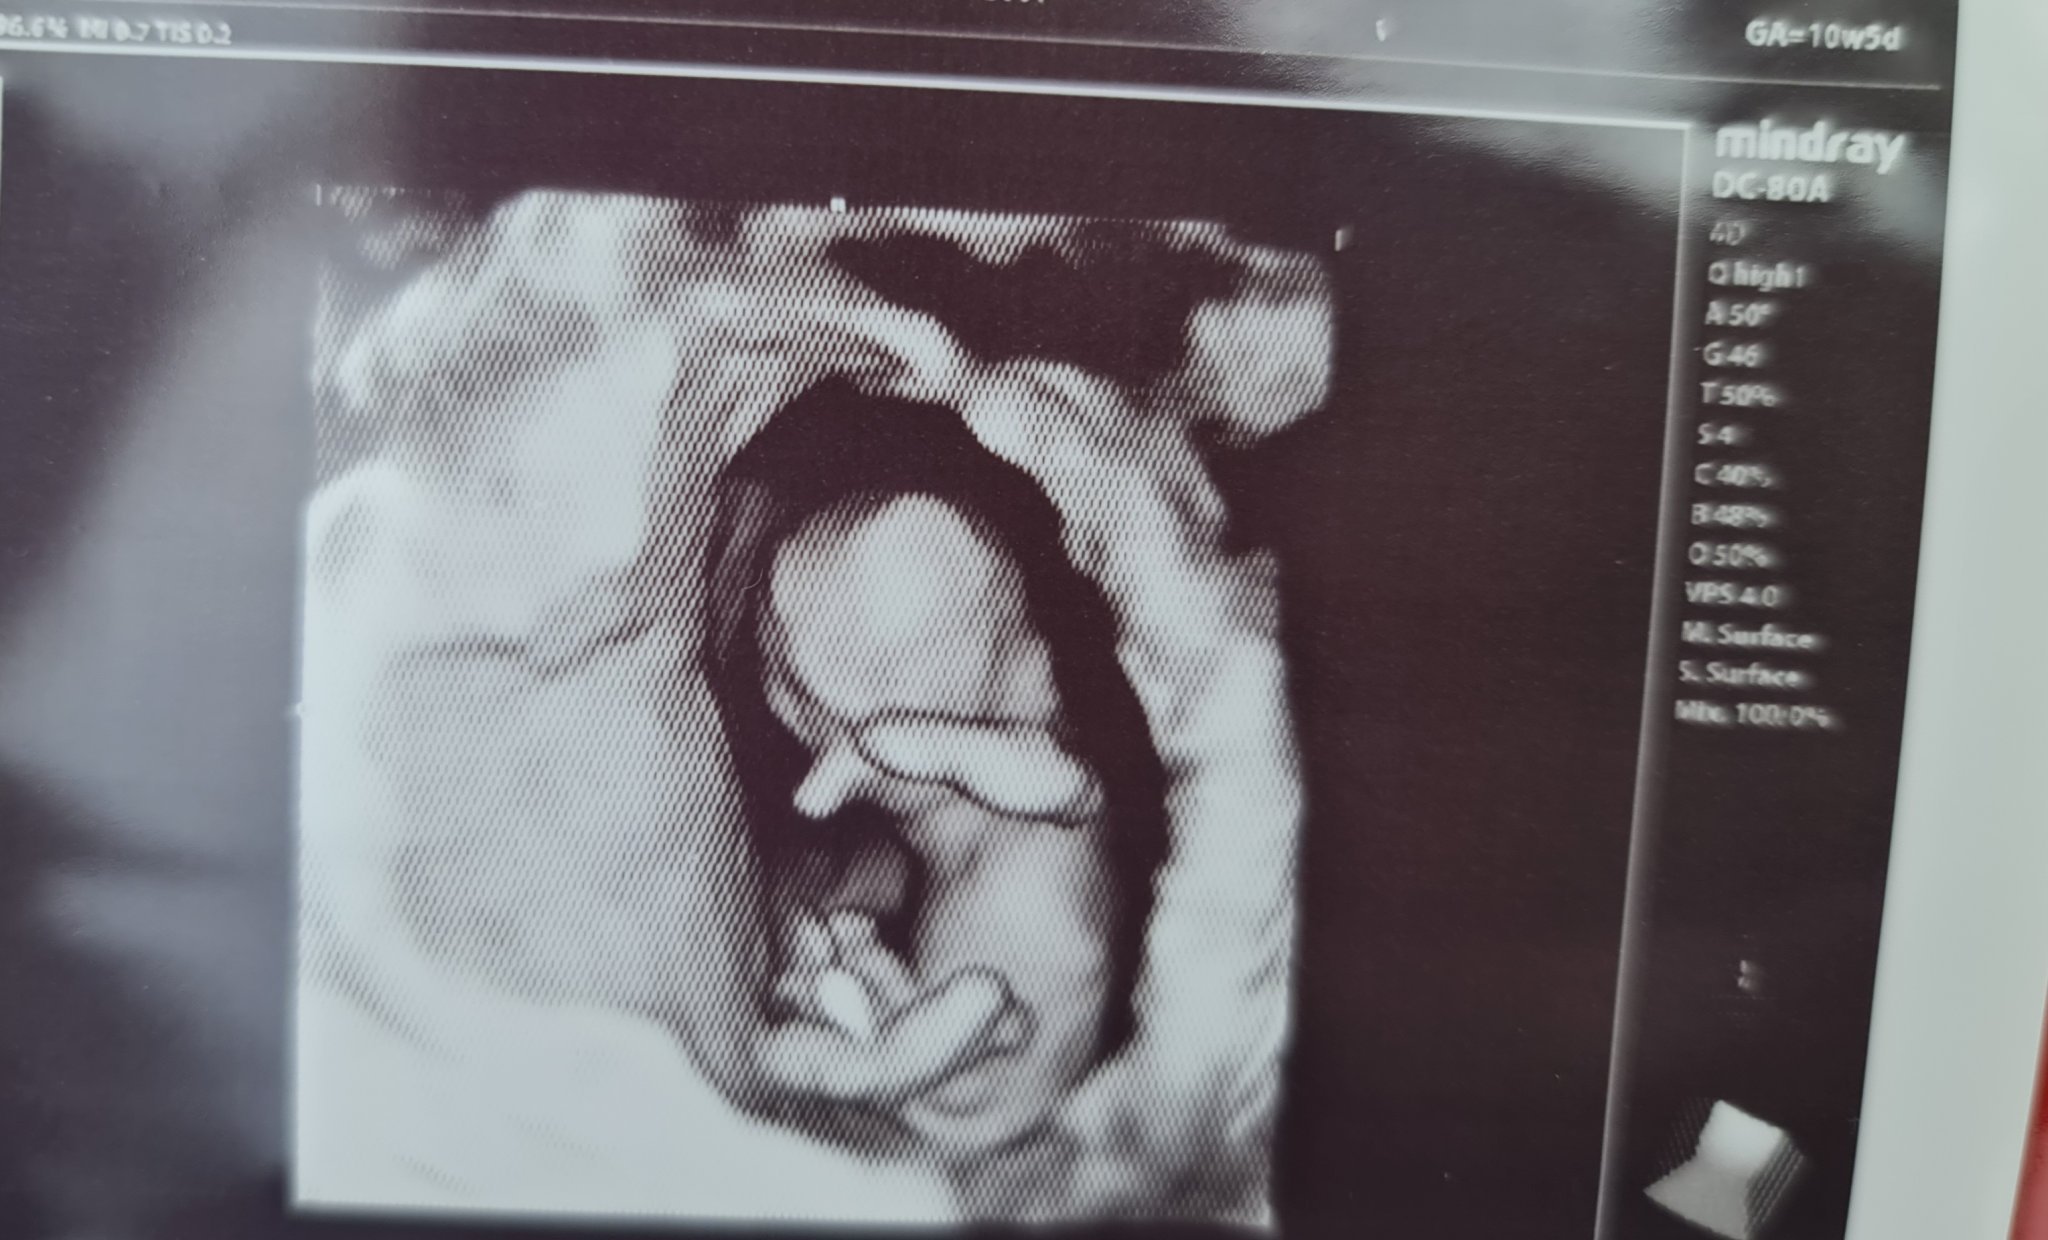

А аз въобще не очаквах на този преглед да получим такава информация, и вика: Да казвам ли,? аз казвам: Да, ако виждате, кажете, а моя мъж се обажда с “Не!”

Та все пак ни каза, че на 80% е момиче според нея

след 2-3 седмици ще се потвърди със сигурност. След едно момче и едно момиче, ми се иска да се окаже права и бебе номер 3 да е момиченце